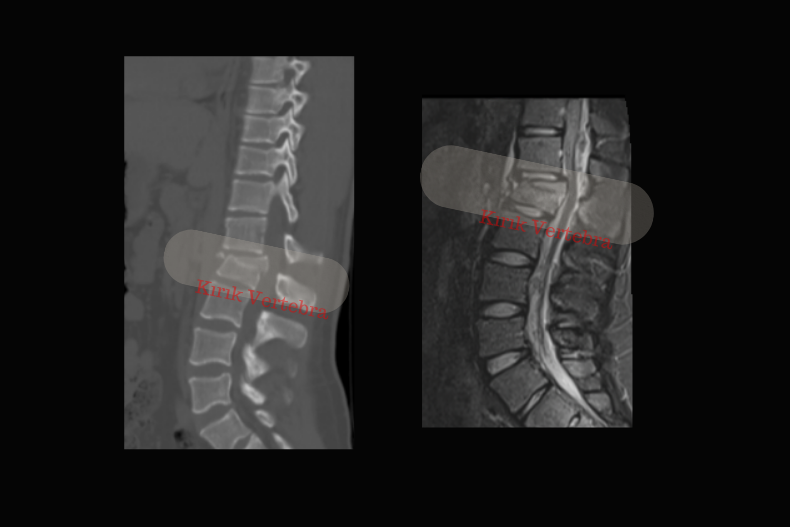

L1 Omurga Kırığı Nasıl Teşhis Edilir?

2. Bilgisayarlı Tomografi (BT)

- Kırığın şekli, yönü ve yayılımı hakkında detaylı bilgi sunar.

- Röntgende görülmeyen küçük kırıkları tespit eder.

- Cerrahi planlama yapılacaksa mutlaka kullanılır.

3. Manyetik Rezonans Görüntüleme (MR)

- Sinir dokusu etkilenmiş mi? sorusuna yanıt verir.

- Omuriliğe veya sinir köklerine baskı, disk hasarı, ödem veya hematom gibi detaylar gösterilir.

- Tümör, enfeksiyon veya osteoporotik kırıklarda tercih edilir.